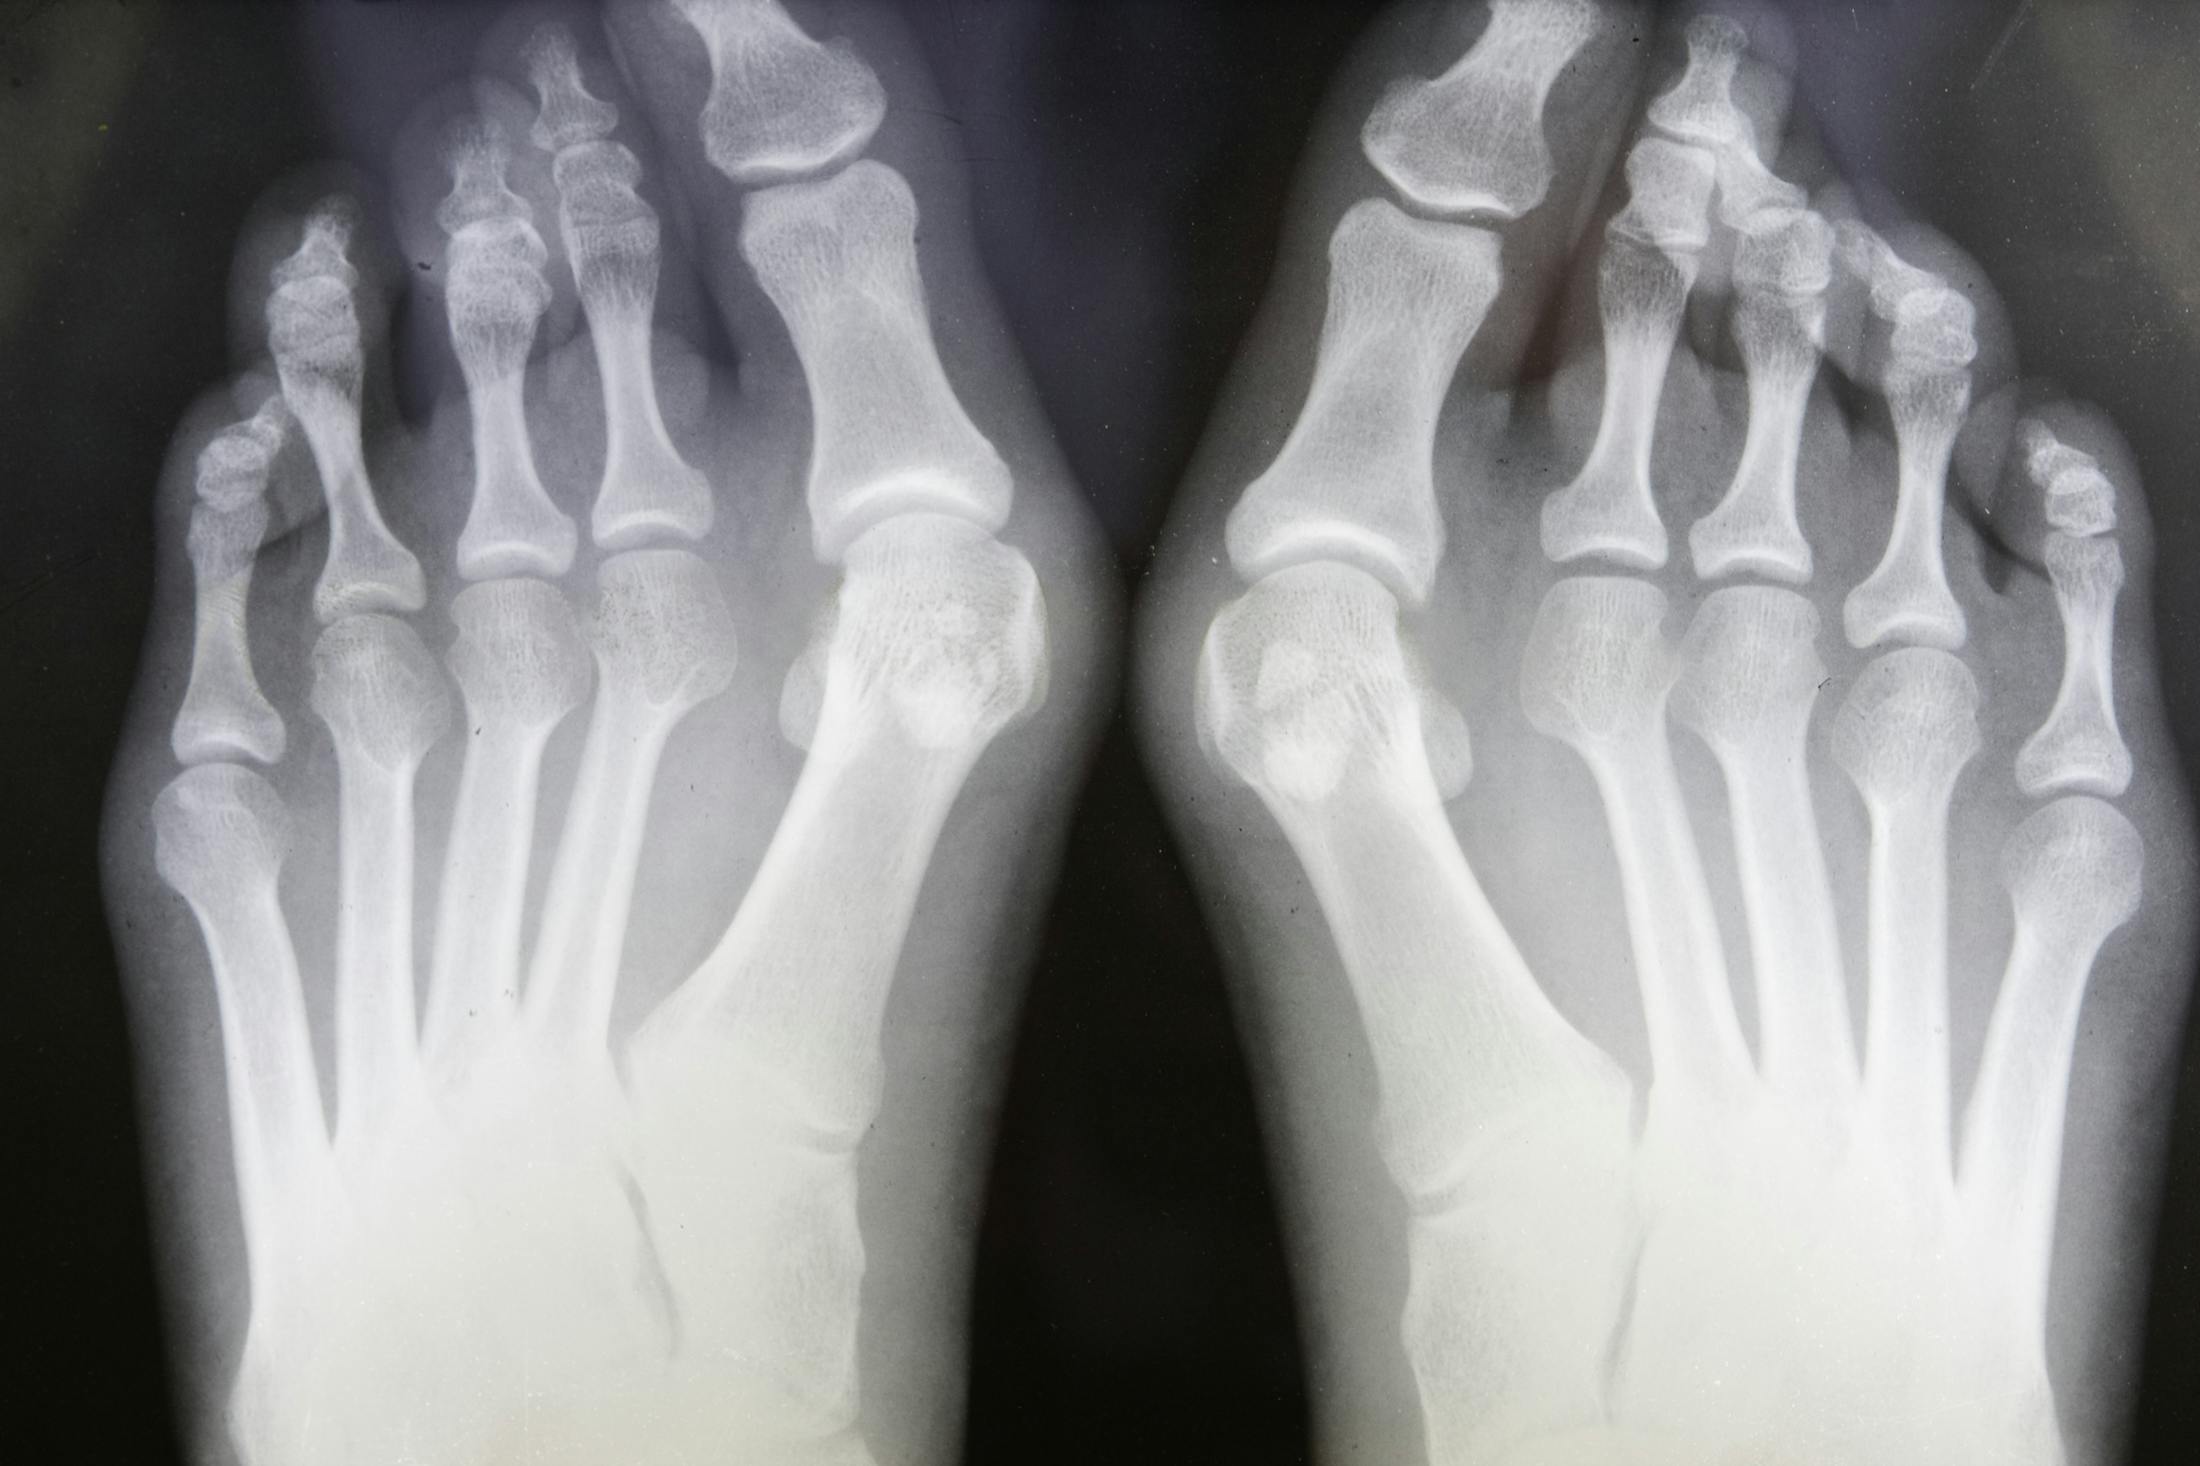

Premier Orthopaedic Associates offers comprehensive care for bunions, from conservative management to advanced surgical solutions, helping patients restore mobility, reduce pain, and regain confidence in everyday activities.

- A visible bump on the side of the big toe joint